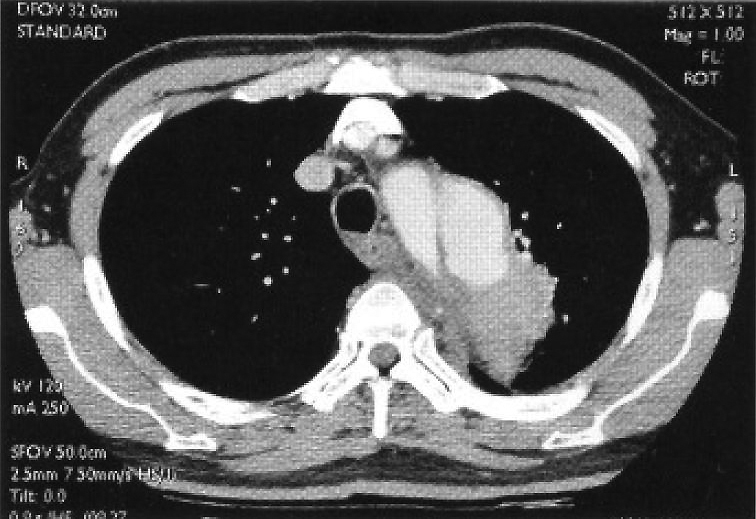

In the third week of postoperative period while the patient was ready for discharge, he suddenly developed massive hemoptysis~ 500ml. A second CXR (Figure 2) was then taken, which showed marked enlargement of the aortic arch. Emergency flexible fibreoptic bronchoscopy demonstrated oozing of blood from apico-posterior segmental bronchi of the left upper lobe, and blood clots in both bronchial trees.

Figure 2: CXR showing enlarged aortic arch

ontrast CT thorax showed a large para-mediastinal mass in the left upper lobe in connection with the aortic arch (Figure 3). There was direct communication between the mass and the aortic lumen via a large focal luminal defect. The large periaortic haematoma extended into the posterior mediastinum, encasing the descending aorta and esophagus (Figure 4). The mass was closely associated with and surrounding the apico-posterior segmental bronchus, with infiltration of adjacent lung parenchyma. The rest of the aorta was pristine without aneurysmal dilatation, dissection or atheroma.

Figure 3: CT thorax showing a huge mass adjacent to aortic arch